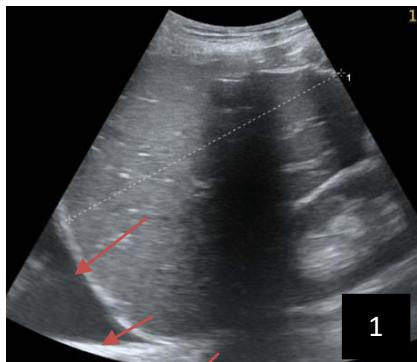

Iconography 1: 54-year-old patient with an intra-splenicsolid mass, anatomopathologically compatible with lymphoma: images 1 and 2: right pleurisy of moderateabundance, image3: celiacadenopathy, image 4: free ascites of moderateabundance, images 5 and 6: intra-splenicsolid mass of around $1418.16\mathrm{ml}$ in B mode and elastographyshowing areas of tumourrigidity, images 7-10: oblique linear images, showingbiopsy gun tracks.